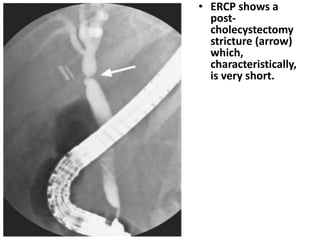

• ERCP shows a

post-cholecystectomy

stricture (arrow)

which,

characteristically,

is very short.

• ERCP showsa post-cholecystectomy stricture (arrow) which, characteristically, is very short.